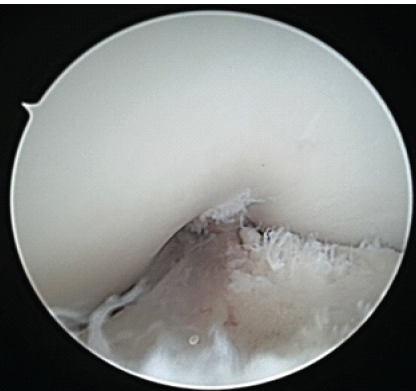

A 12-year-old and 1-month-old premenarchal female presented with a right knee injury after playing basketball when another player collided, striking the patient’s right knee on the outside. The patient sustained a valgus injury to her right knee and felt a pop, followed by pain described as 8 on a scale of 1–10. The patient could not continue playing sports. The pain was described as a dull aching pain, and the patient was unable to bear weight. Patient past medical history was significant for febrile seizures. Patient past surgical history is unremarkable. There were no known drug allergies. The patient did not take any medication. Family history was significant for previous ACL tears with reconstructions in both the mother and father by the senior author 20+ years ago. Physical examination revealed a young female, 60 inches tall and 126 pounds. Here blood pressure was 108/59 with a pulse rate of 90. Initially, the patient had an examination of the non-affected, left knee, which was noted to have no pain to palpation, full range of motion, and ligamentous stability to Lachman’s, posterior drawer, and collateral ligament testing. Next, the patient had an exam of the right knee, revealing knee effusion to visual inspection with tenderness at the lateral femoral condyle to palpation. The patient was guarding and lacked full extension. Lachman’s examination was positive. The patient had a limitation of flexion to 60° limited by pain. The posterior drawer and pivot shift tests were unable to be assessed secondary to pain. The collateral ligaments were stable, and the patient had no calf tenderness and was neurovascularly intact. Three-view radiographs of the right knee were obtained, which did not reveal evidence of fracture. The patient was placed in a knee immobilizer with crutches and was protected weight-bearing with crutches and no sports. Magnetic resonance imaging (MRI) of the right knee was completed 12 days after injury, revealing a complete ACL tear without associated fracture, bone bruise, meniscal tear, or other ligament injury noted. The patient underwent anterior tibial displacement measurement with the knee tester (KT) arthrometer, revealing 7 mm side-to-side difference between the non-involved, left leg (9 mm) and the involved leg, right leg (16 mm) at 30° of flexion. The patient and family had a review of MRI and KT results with very lengthy discussion regarding the risks and benefits of treatment options, including non-operative treatment, ACL repair, and the various types of ACL reconstruction. Due to patient’s young age, premenarchal status, and understanding of the demands required for ACL reconstruction since both parents had undergone ACL reconstruction themselves, the parents desired to proceed with ACL repair understanding that there were no guarantees on relief of pain or restoration of ligamentous healing and knee stability, and consent was obtained. Less than 4 weeks after the injury, the patient underwent ACL repair. The patient was seen in the pre-operative holding area, where she previously received a femoral nerve block. The patient had initials placed on her right knee. The patient was brought to the operating room (OR), where she underwent a general laryngeal mask airway. The patient was placed in a supine fashion on the operative table. The upper extremities and ulnar nerves were well-padded and protected. A tourniquet was applied to the right proximal thigh area. The patient was placed in a Stryker leg holder. No tourniquet was used. The left lower extremity was well-padded on a blanket and pillow. A time-out was performed with confirmation of antibiotics. We began by injecting respective anteromedial and anterolateral portal sites with 10 mL of 0.25% bupivacaine with epinephrine. The patient then had portals developed. The scope was inserted laterally. On entering, the patellofemoral joint appeared to be intact. The fat pad was debrided for visualization of the ACL midsubstance tear, with mop ends noted (Fig. 1).

Figure 1: Intraoperative arthroscopic image from the anterolateral portal of the right knee with 30° arthroscope showing mid-substance anterior cruciate ligament rupture. Note torn mop ends of tibial stump.